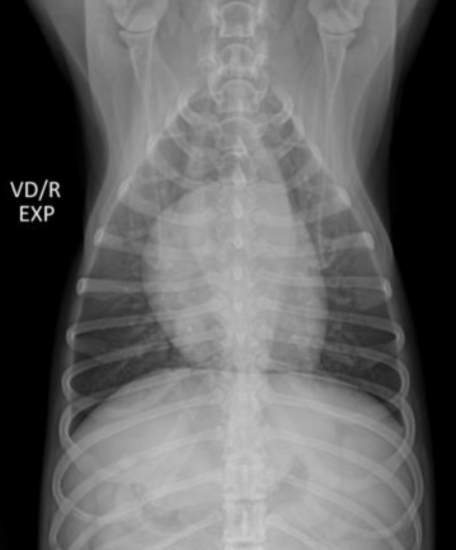

| Normal variation |

|---|

Thymus (sail sign)![]() - 어린 동물에서 thymus가 남아있는 모양을 “sail sign”이라고 함. (모양은 다양) |

| Skin fold - 기흉과 헷갈리게 생겼지만, 자세히 보면 바깥이랑 이어지고 있음. |

CCJ (costso-chondral junction) ![]() - 폐결절과 오인하지 않도록. - 닥스훈트에서는 꺾어서 관절하기 때문에 더 두드러짐. |